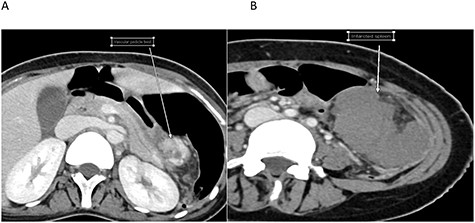

Upon reviewing her file, she had a CT scan done two years prior to this presentation for an abdominal pain and it confirmed the diagnosis of WS; however, no treatment options were offered to her with no follow-ups (Fig. 2).

Cross-sectional image at the time initial diagnosis shows normal enhancement.